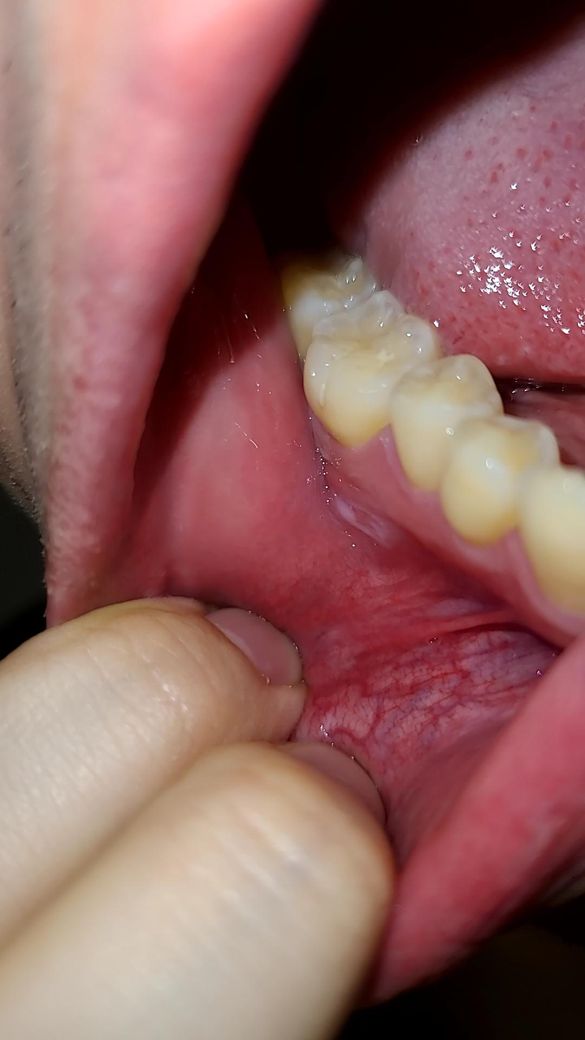

구내염 인지 뭔가가 좀 오래지속되는데요 구강암인가요

1주 더지나서 오늘 보니까 하얀게 보이네요

불편한건 더 심해졌어요

• 2번 째 사진

악성병소보다는 구내염에 가까운 것으로 사진상 보이는데요

오라메디 적용해보시고 호전되지 않으면 구강내과 가보세요